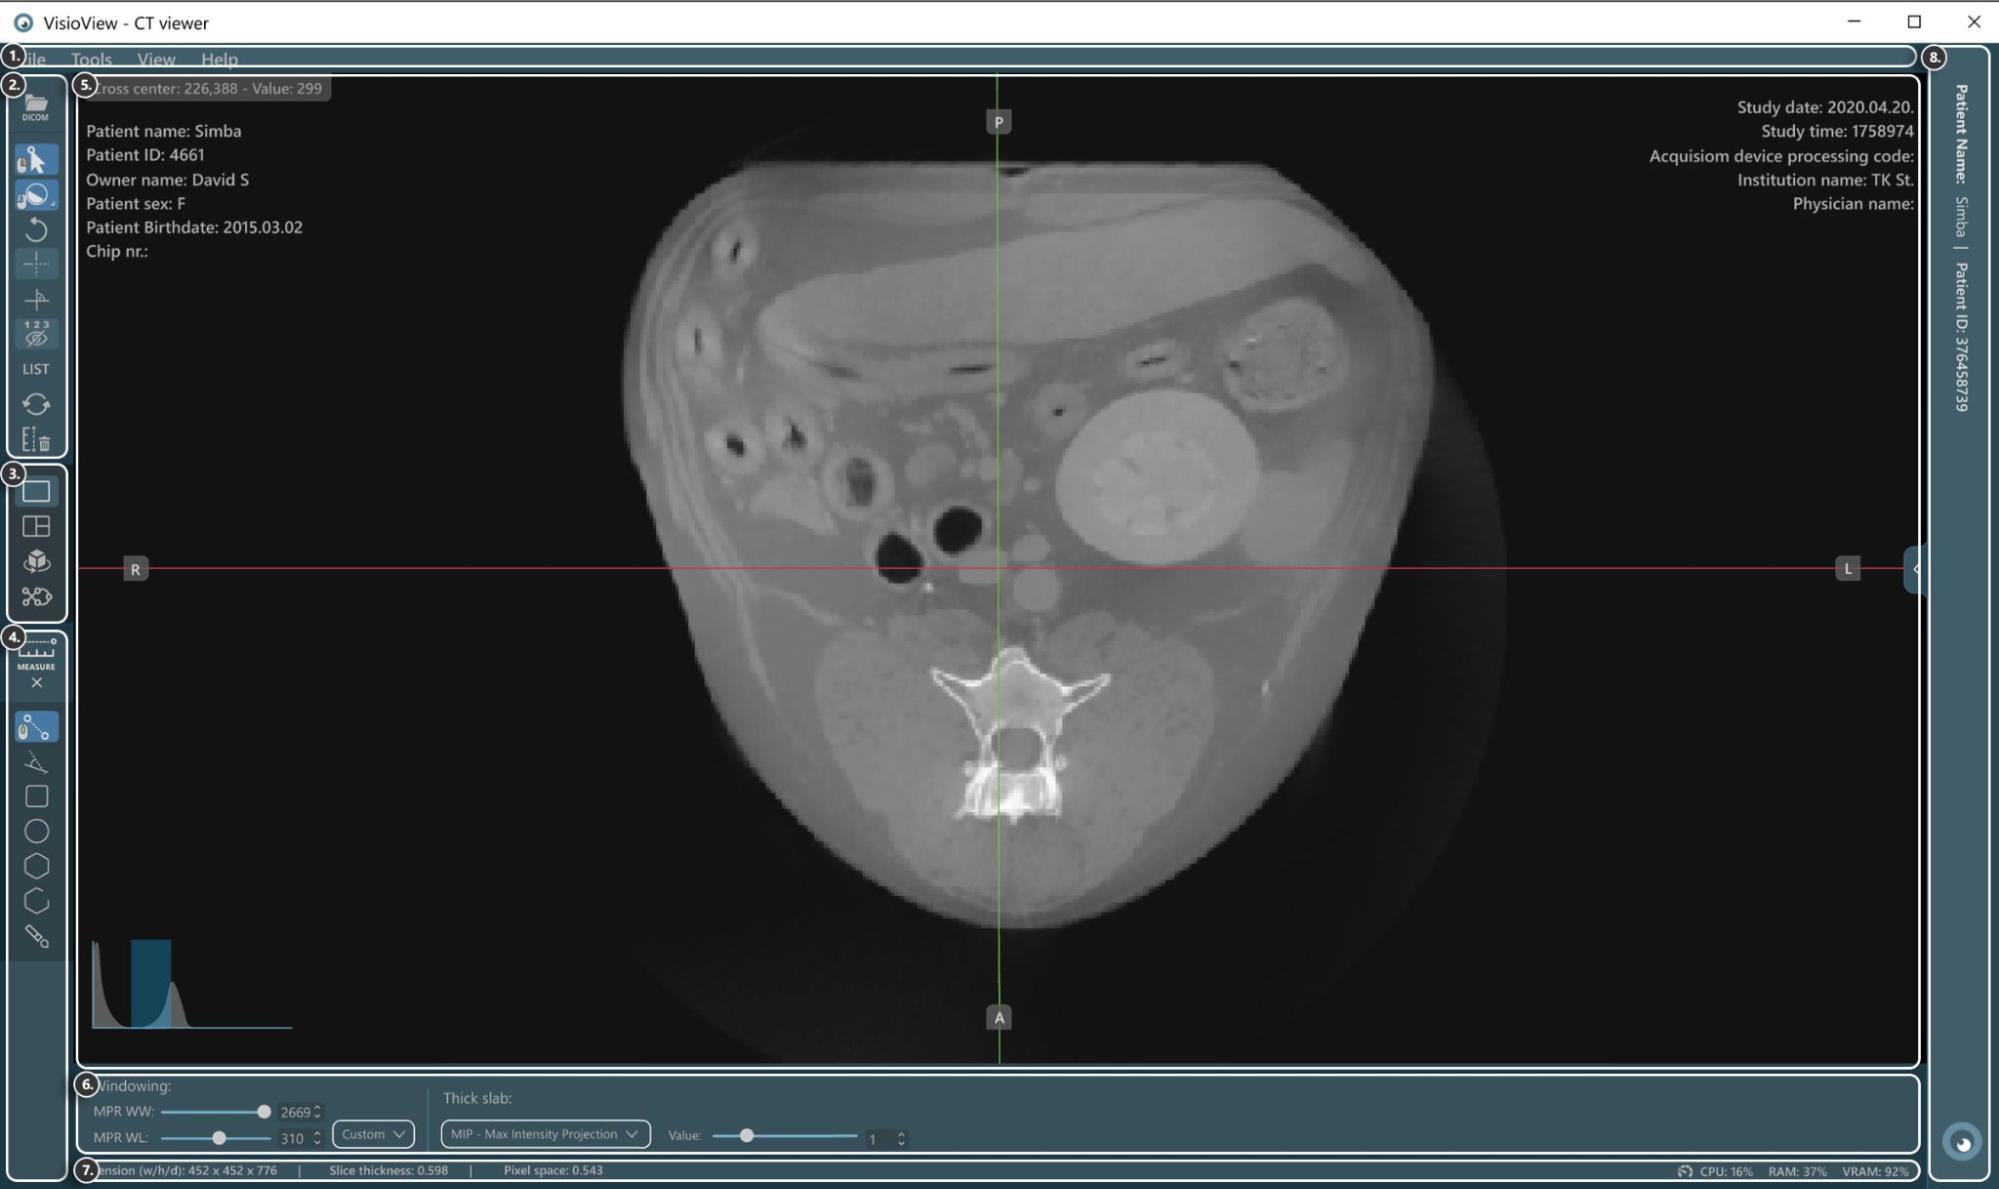

Sections of the VisioVIEW CT Viewer¶

The VisioVIEW CT Viewer consists of several sections, each tailored to a specific purpose. Below is a detailed description of each section.

Load DICOM file

Select item

Windowing tool (Default, Dynamic, or choose from existing windowing presets)

Rotate image

Hide/Show slicers

Perpendicular/Separate slicers

Hide/Show measurement information

Open measurement list

Restore image transformations to default

Delete all measurements

View Selector¶

Measurement Tools¶

Show/Hide measurement tools

Distance measurement

Angle measurement

Rectangle measurement

Oval measurement

Polygon measurement

Path length measurement

Brush tool

Viewer Area¶

HU (Hounsfield Unit) pixel value

Patient information

Windowing histogram tool

Slicers

Study information

View Settings and Options¶

Windowing settings

Thick slab settings

Information Bar¶

DICOM image and resolution information

Performance and resource usage information